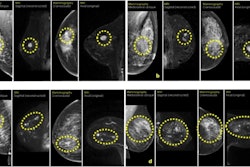

Abbreviated MRI may be suitable for screening women with dense breasts, a study published May 22 in the American Journal of Roentgenology found.

Researchers led by Christine Edmonds, MD, from the University of Pennsylvania in Philadelphia, found that subsequent rounds of abbreviated breast MRI screening in patients with dense breasts had lower abnormal interpretation rates compared with baseline examinations. Meanwhile, high cancer detection rates were also maintained.

Previous studies have demonstrated abbreviated breast MRI’s performance in high cancer detection rates when applied for baseline supplemental screening in women with dense breasts. However, the researchers noted that limited data is available on the modality’s performance in subsequent screening rounds.

Edmonds and colleagues compared outcomes between baseline and subsequent rounds of screening abbreviated MRI in women with dense breasts. The women otherwise had an average risk of developing breast cancer.

The retrospective study included data collected between 2016 and 2023 for 2,585 abbreviated MRI exams. Of the total, 2,007 were baseline exams while 578 were subsequent-round exams. The exams were performed for supplemental screening in 2,007 women with dense breasts with an average age of 57.1 years.

Among baseline exams, 1,658 (82.6%) were categorized as BI-RADS 1 or 2, 171 (8.5%) were BI-RADS 3, and 178 (8.9%) were BI-RADS 4 or 5. For subsequent-round exams, 533 (92.2%) were BI-RADS 1 or 2, 20 (3.5%) were BI-RADS 3, and 25 (4.3%) were BI-RADS 4 or 5 (p < 0.001).

The researchers also reported a higher abnormal interpretation rate among baseline exams compared to subsequent-round exams, as well as comparable positive predictive values and cancer detection rates between the two exam types.